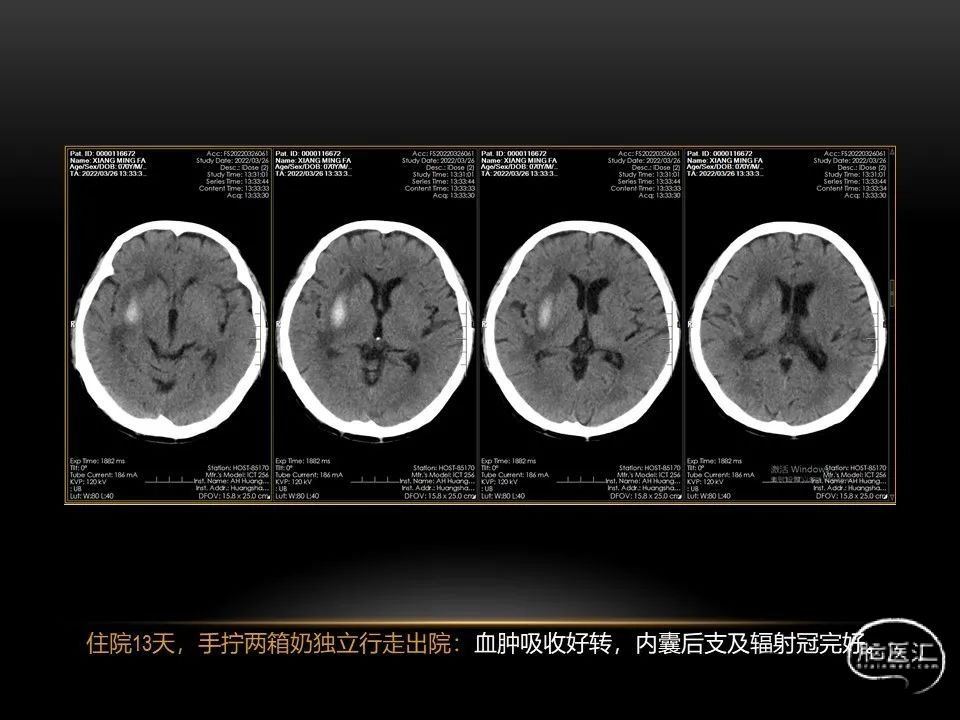

相近的脑出血量,

发生在不同部位有截然不同的症状,

同样也决定了预后也是截然不同的。

自发性脑出血不仅仅累及内囊后肢才会出现偏瘫及偏身感觉障碍,病变累及大脑脚或辐射冠同样有可能有类似症状和体征。内囊、辐射冠、大脑脚等结构之间是延续的,只是不同区域不同名称而已。定位诊断需要对解剖结构概念清晰,读片准确辨认,灵活掌握。

每位患者的病情都不完全一样,唯有通过不断积累、仔细分辨、细心总结,方能沉着应对,为患者造福。本人水平有限,有空就收集一些手头珍贵资料分析分析,总结总结,回味回味,总会发现很多不懂的,总会有新的收获。望老师和朋友们不吝赐教,给我留言交流心得。